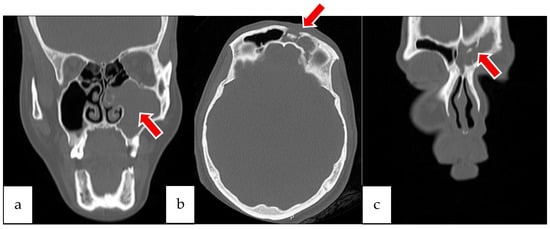

2.2. Case 2